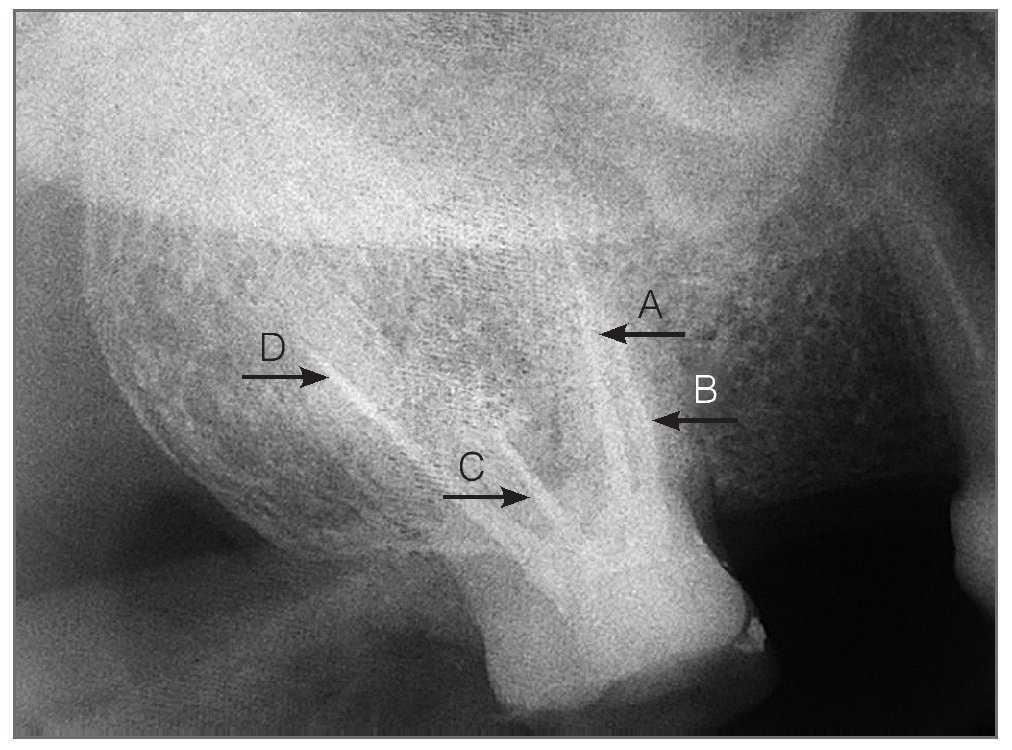

Figura 4a. Ajuste de las 4 puntas de gutapercha. (A) vestibulomesial; (B) palatino accesorio; (C) vestibulodistal; (D) palatino principal.

Figura 4b. Obturación de los 4 conductos radiculares con gutapercha. (A) vestibulomesial; (B) palatino accesorio; (C) vestibulodistal; (D) palatino principal.